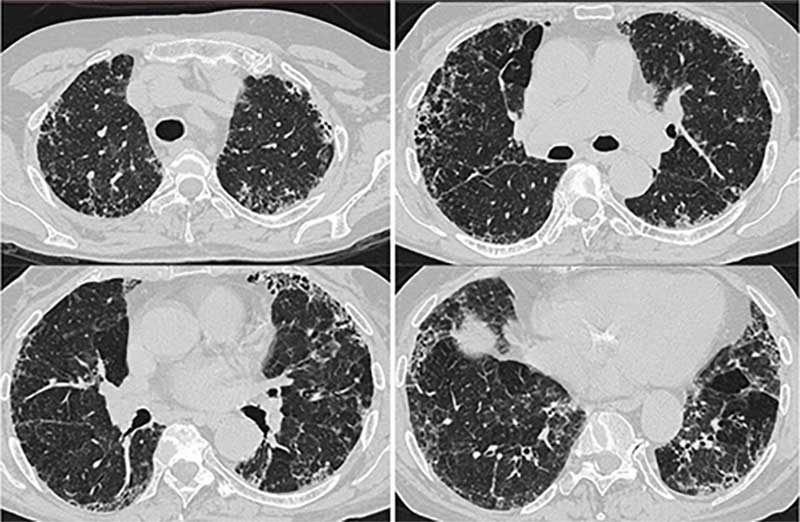

Es gibt vielfältige morphologische Erscheinungsbilder der Erkrankung in der Lunge mit Überlappungen zu anderen Erkrankungen. Die Diagnose in der Computertomographie kann deshalb anspruchsvoll sein. Dabei ist unklar, warum sich die Sarkoidose im Einzelfall so unterschiedlich verhält – abgesehen von der Frage der Organbeteiligung. Die Verlaufsformen werden in akut oder chronisch eingeteilt. Akute Formen der Sarkoidose beginnen häufig mit Gewichtsverlust, Abgeschlagenheit, Nachtschweiß oder Temperaturen 37,5°C bis 37,9°C (subfebril). Die Kombination von Gelenkschmerzen, bläulichem Hautausschlag und Fieber ist als sogenanntes Löfgren-Syndrom bekannt. Entzündungsparameter im Blutserum schließen eine erhöhte Konzentration von Interleukin-2-Rezeptoren ein. Die akute Sarkoidose betrifft neben der Lunge oft weitere Organe, z.B. lymphatische Organe, Milz, Leber und Knochenmark. Akute Verlaufsformen ohne Beteiligung der Milz tendieren zur Spontanheilung (Spontanremission). Wiederauftreten (Rezidive) manifestiert sich hingegen meistens mit akuten Symptomen.

Die Diagnose erfolgt anhand: typischer Hautveränderungen, Lymphknotenvergrößerungen, morphologischer Veränderungen der Lunge in der Computertomographie und / oder des Nachweises von Sarkoidose-Granulomen im Gewebe. Besonders die Abgrenzung zu anderen Systemerkrankungen kann erhebliche Probleme aufwerfen, auch nach histologischer Abklärung. Das spezialisierte ILD-Board entscheidet interdisziplinär, welche diagnostische Methode wir im Einzelfall heranziehen.